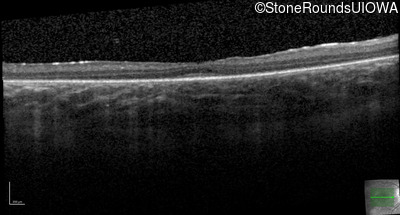

Optical Coherence Tomography - Right - 20/100

Exemplar / OCT Stack